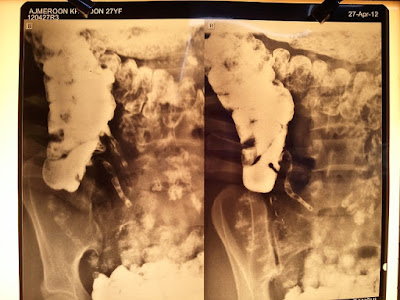

Today being Thursday, I was trying to get some amount of sleep when our chowkidar came knocking. Titus had sent me a chart. The patient's relatives could not pay the total bill. . . Well - the diagnosis. Obstructed labour caused by hydrocephalus resulting in a rupture uterus and a rupture bladder. The bladder rupture was too bad that Nandamani had to put in an patch of omentum to give some sort of structural integrity to the bladder. . .